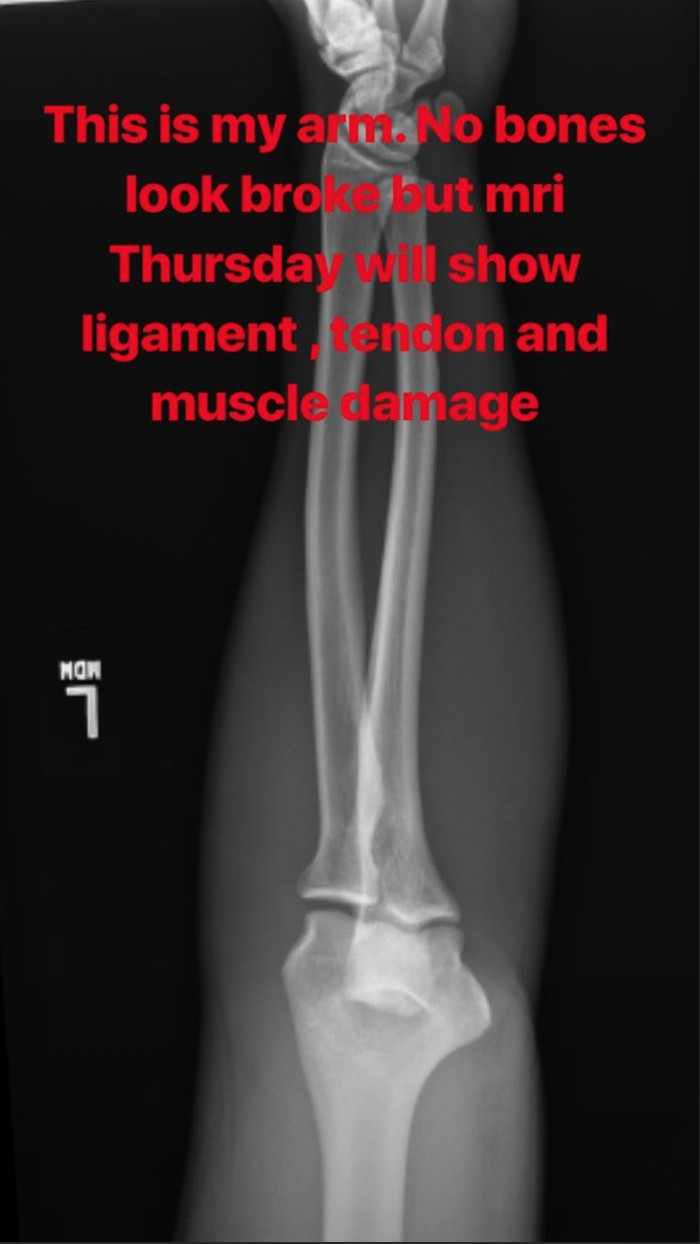

Perry разкри рентгенова снимка, на която се вижда, че няма счупвания. На него все пак му предстои да се подложи на скенер, за да се види дали няма щети по сухожилията, мускулите и прочие - може там да има нещо.